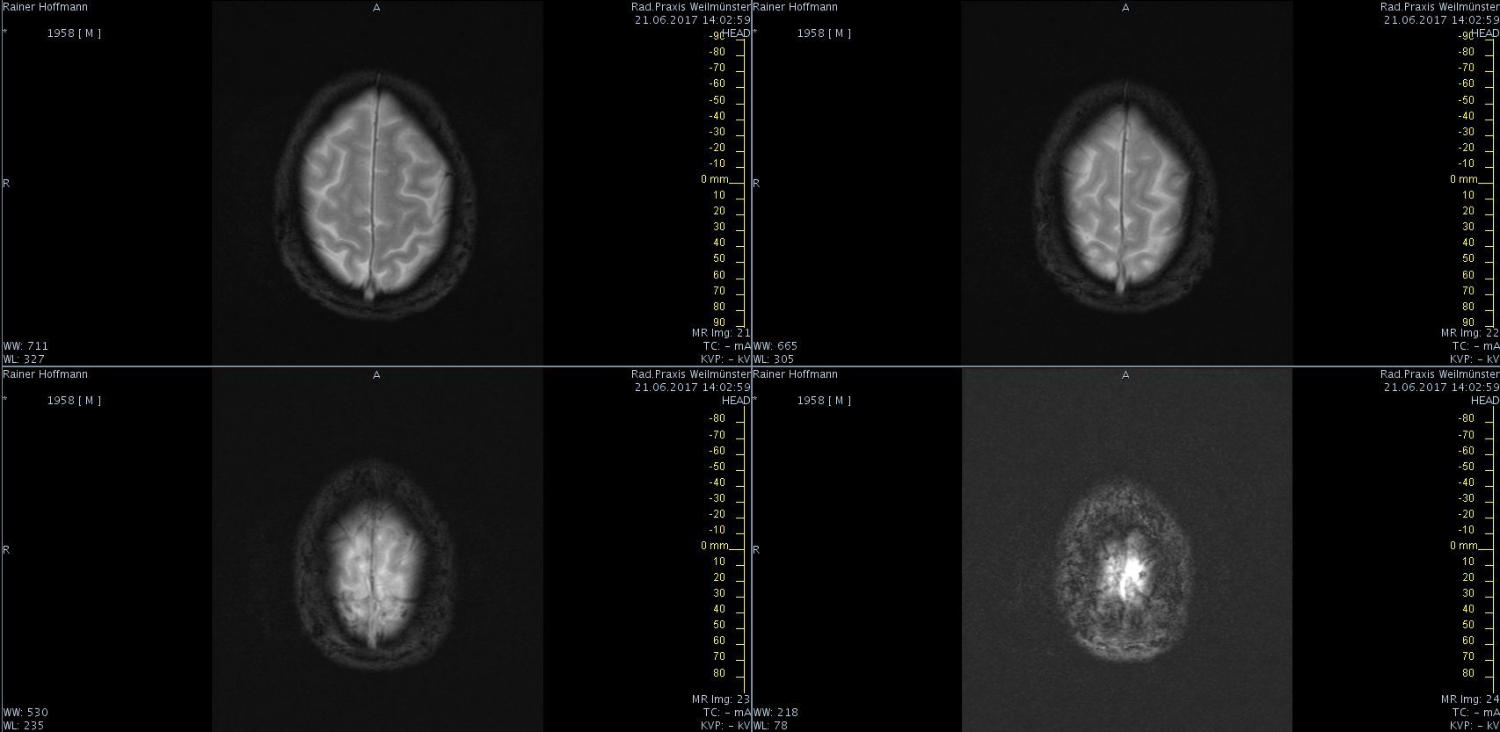

Das ist ja ganz toll, dass Ihr die Seite so schnell gefunden habt. Ich zeige euch jetzt ein ganz, ganz anderes Paßfoto von mir. Es könnte Ähnlichkeiten zu anderen lebenden oder bereits verstorbenen Personen geben. Wenn Ihr das erste Bild oben links anklickt wird es ver- größert dargestellt. Dann kann man mit den Pfeiltasten am unteren Bild- rand durch meinen Kopf blättern. Es gibt nicht viel zu sehen. Vielen Dank an Martina für Ihre Hilfe.

MRT